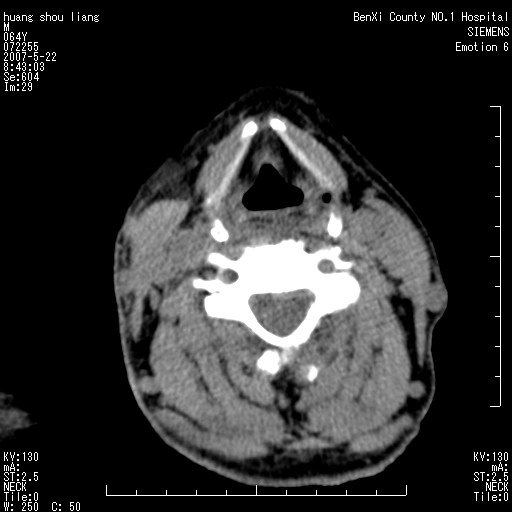

男性,64岁。颈部包块8年。最近增大。

对不起大家,可能是片子发太多有点乱,正常腮腺在下颌角的外侧,颌下腺在下颌体的中部内侧,本例在下颌角内侧偏下,和腺体一点关系都没有,从vrt和mpr上可以很明显看出来,再者肿块是好多粘连在一块的,大家在仔细看看,左侧可能也是吧,我还是考虑为肿大的淋巴结融合在一块,但性质??????

右侧腮腺下部均匀软组织密度肿块,外形不规则,与周围组织分界清晰,考虑右侧腮腺混合瘤或多形性腺瘤。

大家好,病理结果出来了,如大家所说,颌下腺混合瘤。

唉,解剖没学好吧,我诊断错了,不过还是有些不理解回去我在多看看书,谢谢大家的参与,以后我还会奉献好的病例。